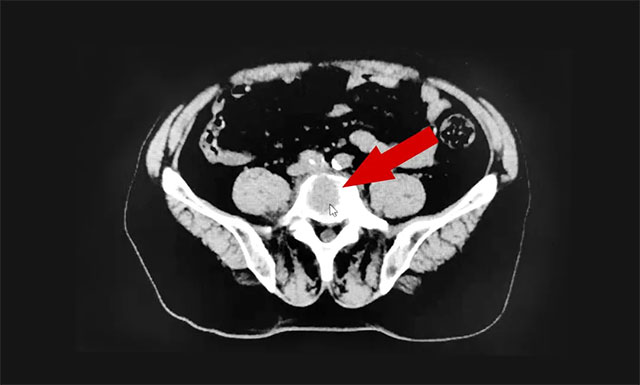

▲ 患者腰椎部出現(xiàn)轉移性骨腫瘤